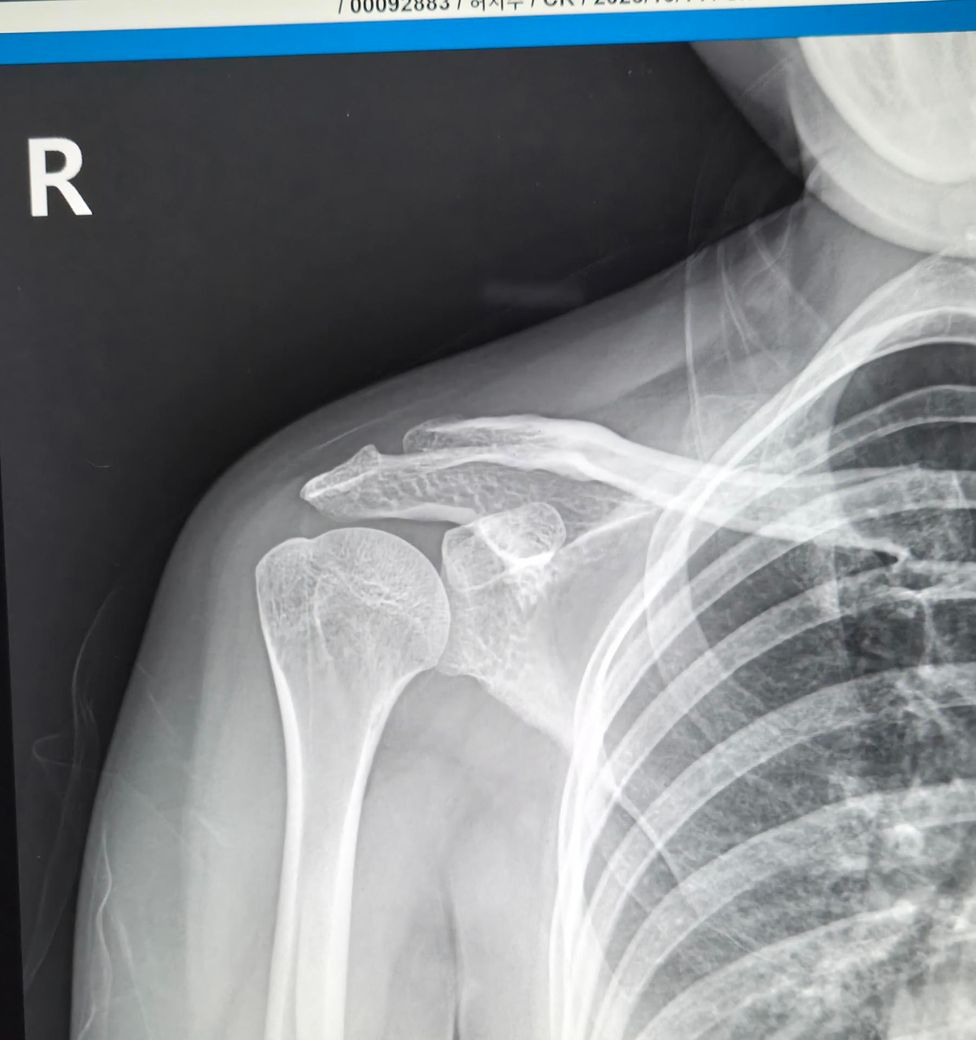

2024년도에 전동차가 전복되면서 왼쪽어께 다치면서 어께가 많이 안좋아요.

2025년10월14일 찍은 오른쪽,왼쪽어께사진이랑

2026년2월19일 목요일 오른쪽,왼쪽어께사진이랑

비교해주세요.왼쪽어께가 찌릿하고 통증있어요.

2025년도 찍은거랑 2026년 찍은거랑 차이 많이 나보이죠?

• 3번 째 사진

비교해보면 뼈의 정렬이나 관절간격,건봉모양 같은 기본부조는 크게 달라진 부분이 없어보입니다. 짧은시간사이에 관절이 급격히 닳았다거나 뼈가 무너졌거나 하는 진행성 변화는 뚜렷하지 않습니다. 다만 원래부터 견봉아래 공간이 약간 좁은 구조라서 회전근대 힘줄이 지나가는 공간이 넉넉한 편은 아니고,이런 해부학적 형태는 시간이 지나면서 염증이나 충돌증상이 반복될 가능성은 있습니다. 마지막 MRI 단면을보면 회전근개 힘줄부위에 염증또는 부분손상으로 의심되는 신호변화가 보입니다.염증,부분파열 또는 퇴행성 변화기능성이 있습니다. 이런경우 팔을 90도이상 올릴때 통증이 심해지는 양상이 흔합니다. 빠른쾌유를 빕니다!

오른쪽은 비교적 차이가 없지만 왼쪽은 살짝 차이가 있습니다.

사진만으로 보면 "2025년 대비 2026년 X-ray에서 뼈 위치가 크게 변했다거나 탈구.골절이

새로 생긴 차이는 뚜렷하지 않습니다."

다만 X-ray는 "근육.힘줄.회전근개.신경 문제를 거의 못 봅니다" 찌릿한 통증은 이런 연부조직/신경 원인이 흔해요.

전동차 전복 외상 병력이 있고 통증 지속이면 "회전근개 손상, 충돌증후군, 경추 연관통" 가능성 있습니다.

“차이가 많이 난다”기보단 "X-ray로는 한계가 있고, MRI가 꼭 필요한 상황"으로 보입니다.